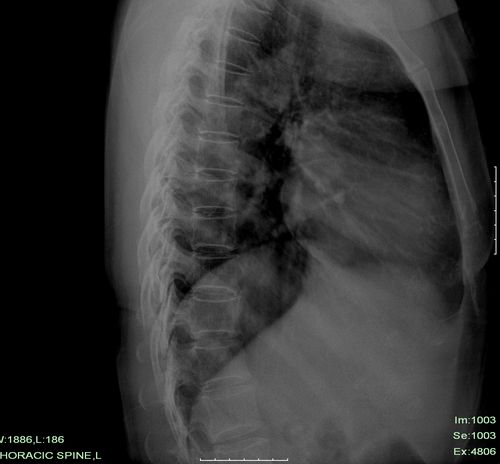

标题: 侧位片

男性还是女性?要是男性乳房影也忒发达了!胸片双肺未见明显异常,侧位片示主动脉管径增宽;kub未包括盆腔,片内未见明显气液平面及膈下游离气体。